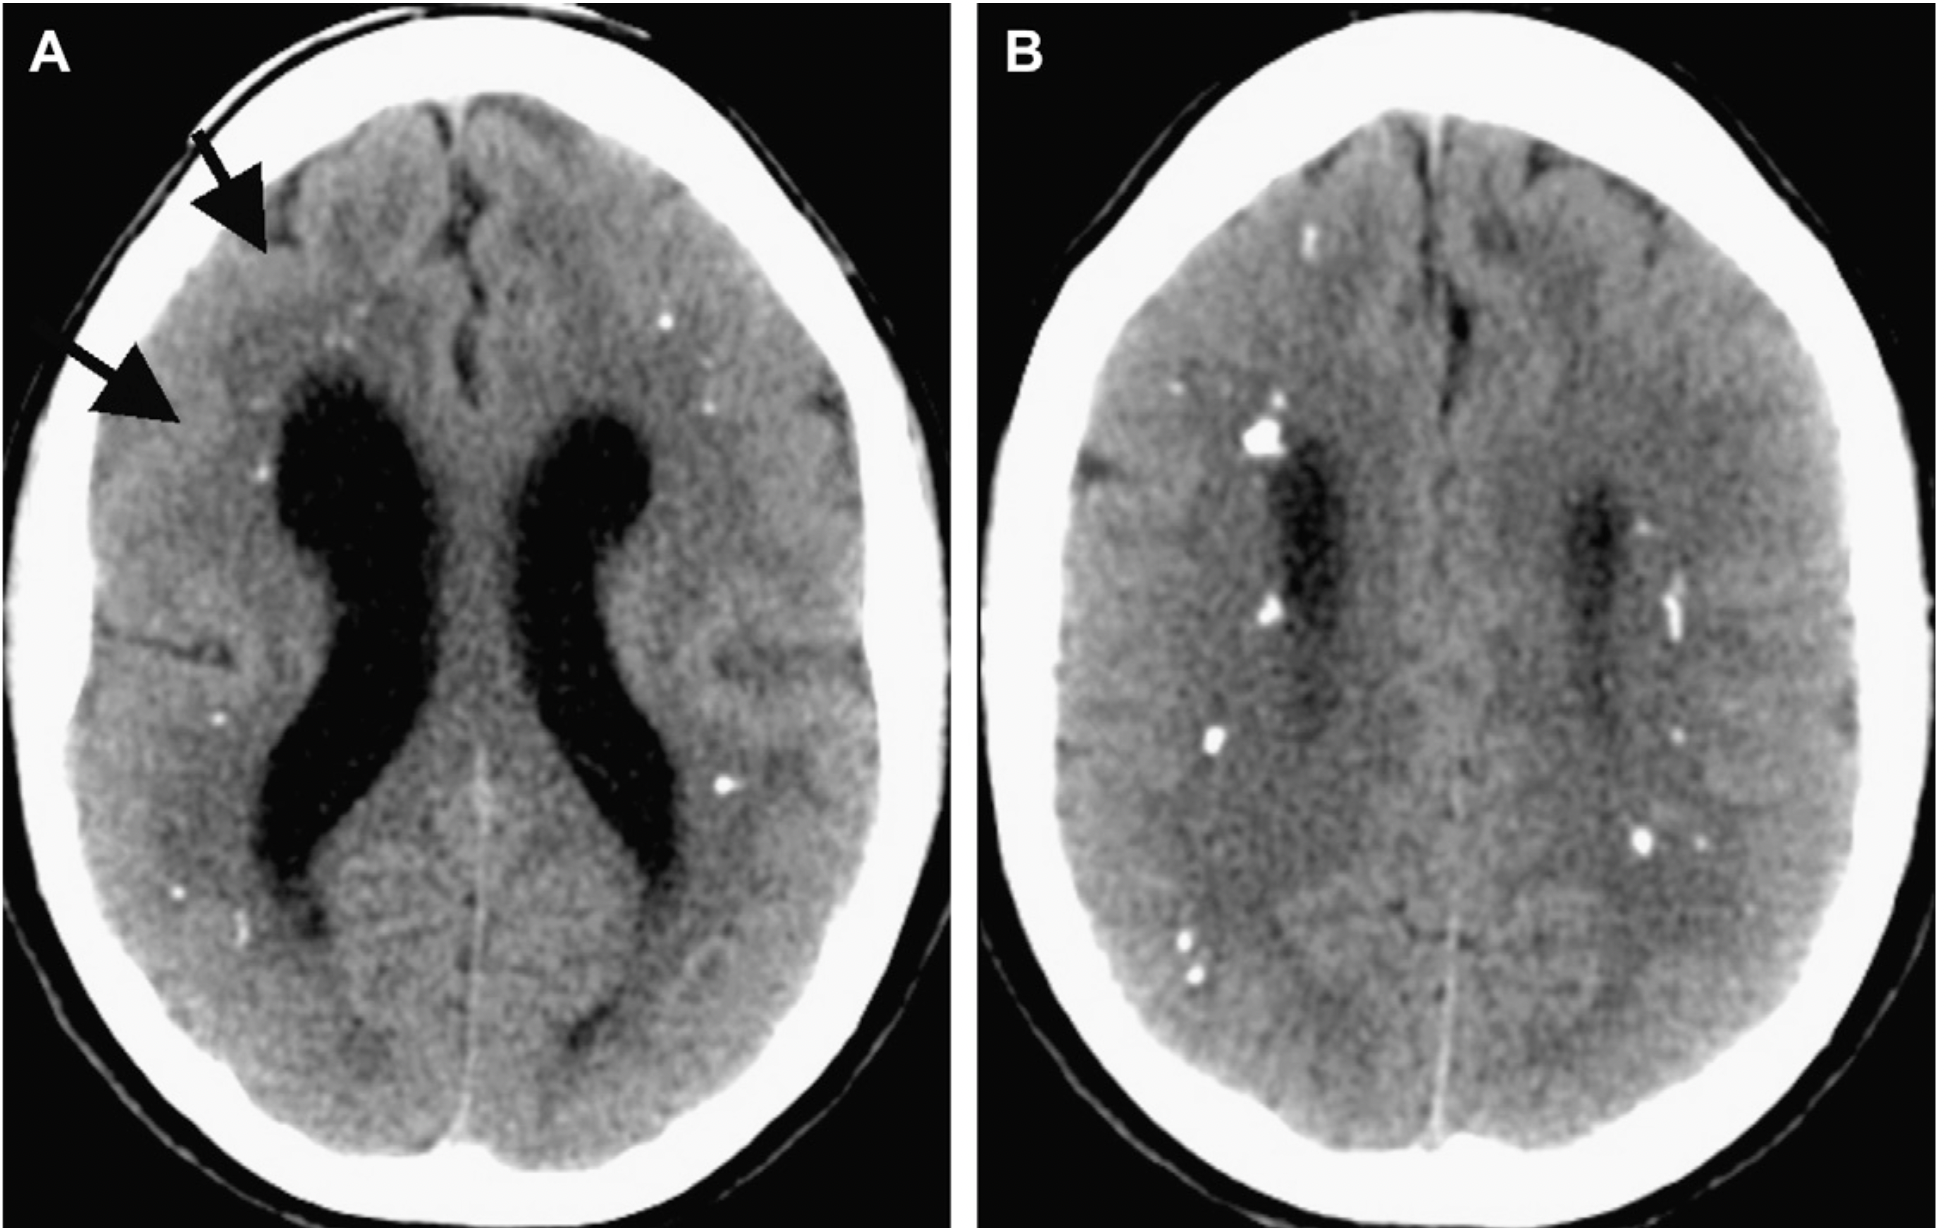

미 전역에서 최근 어린이 환자의 세균성 뇌질환 감염이 늘어나는 것이 코로나19와 관련 가능성이 높다는 연구결과가 나왔다. 질병통제예방센터 CDC가 지난 5일 발표한 질병 및 사망률 주간 보고서(Morbidity and Mortality Weekly Report- 원문클릭)에 따르면 미시건 어린이 병원에서 코로나19 펜대믹 중 세균성 뇌감염 소아환자가 236% 증가했다. 이들 대부분은 12세 미만 유아 및 어린이게서 발생했으며 이들 중 상당수가 SARS-CoV-2 바이러스 감염됐다.

CDC와 연구진들은 코로나 19 팬데믹 초기 2년 동안(2020년 3월 ~ 2022년 3월) 유사한 사례가 발생했는지 확인하기 위해 약 2,800개 감염병 네트워크인 미국 감염네트워크를 통해 설문조사를 실시했다. 연구진들은 109개 병원을 조사한 결과 47개(43%) 병원에서 코로나19 팬데믹 2년동안 18세 미만 환자에게게서 머리 안쪽에서 세균감염 증가가 관찰됐다고 보고했다.

이같은 사례를 통해 미국감염네트워크 연구진은 코로나19 바이러스가 면역체계를 약화시켜 구강내에 있던 박테리아가 뇌로 이동 했을 가능성에 주목하고 머리내 세균성 뇌질환이 코로나19와 연관이 있다는 가설을 제시했다.

가설을 제시한 연구진들은 “뇌감염 증가는 어린이들이 코로나19 감염이후 정상적 치료를 받지 못했거나 백신접종을 하지 않았기 때문일 수 있”면서 “자녀들에게서 이유없는 두통이 생기거나 행동변화를 보일경우 소아과 전문의를 찾아야 한다”고 조언한다.